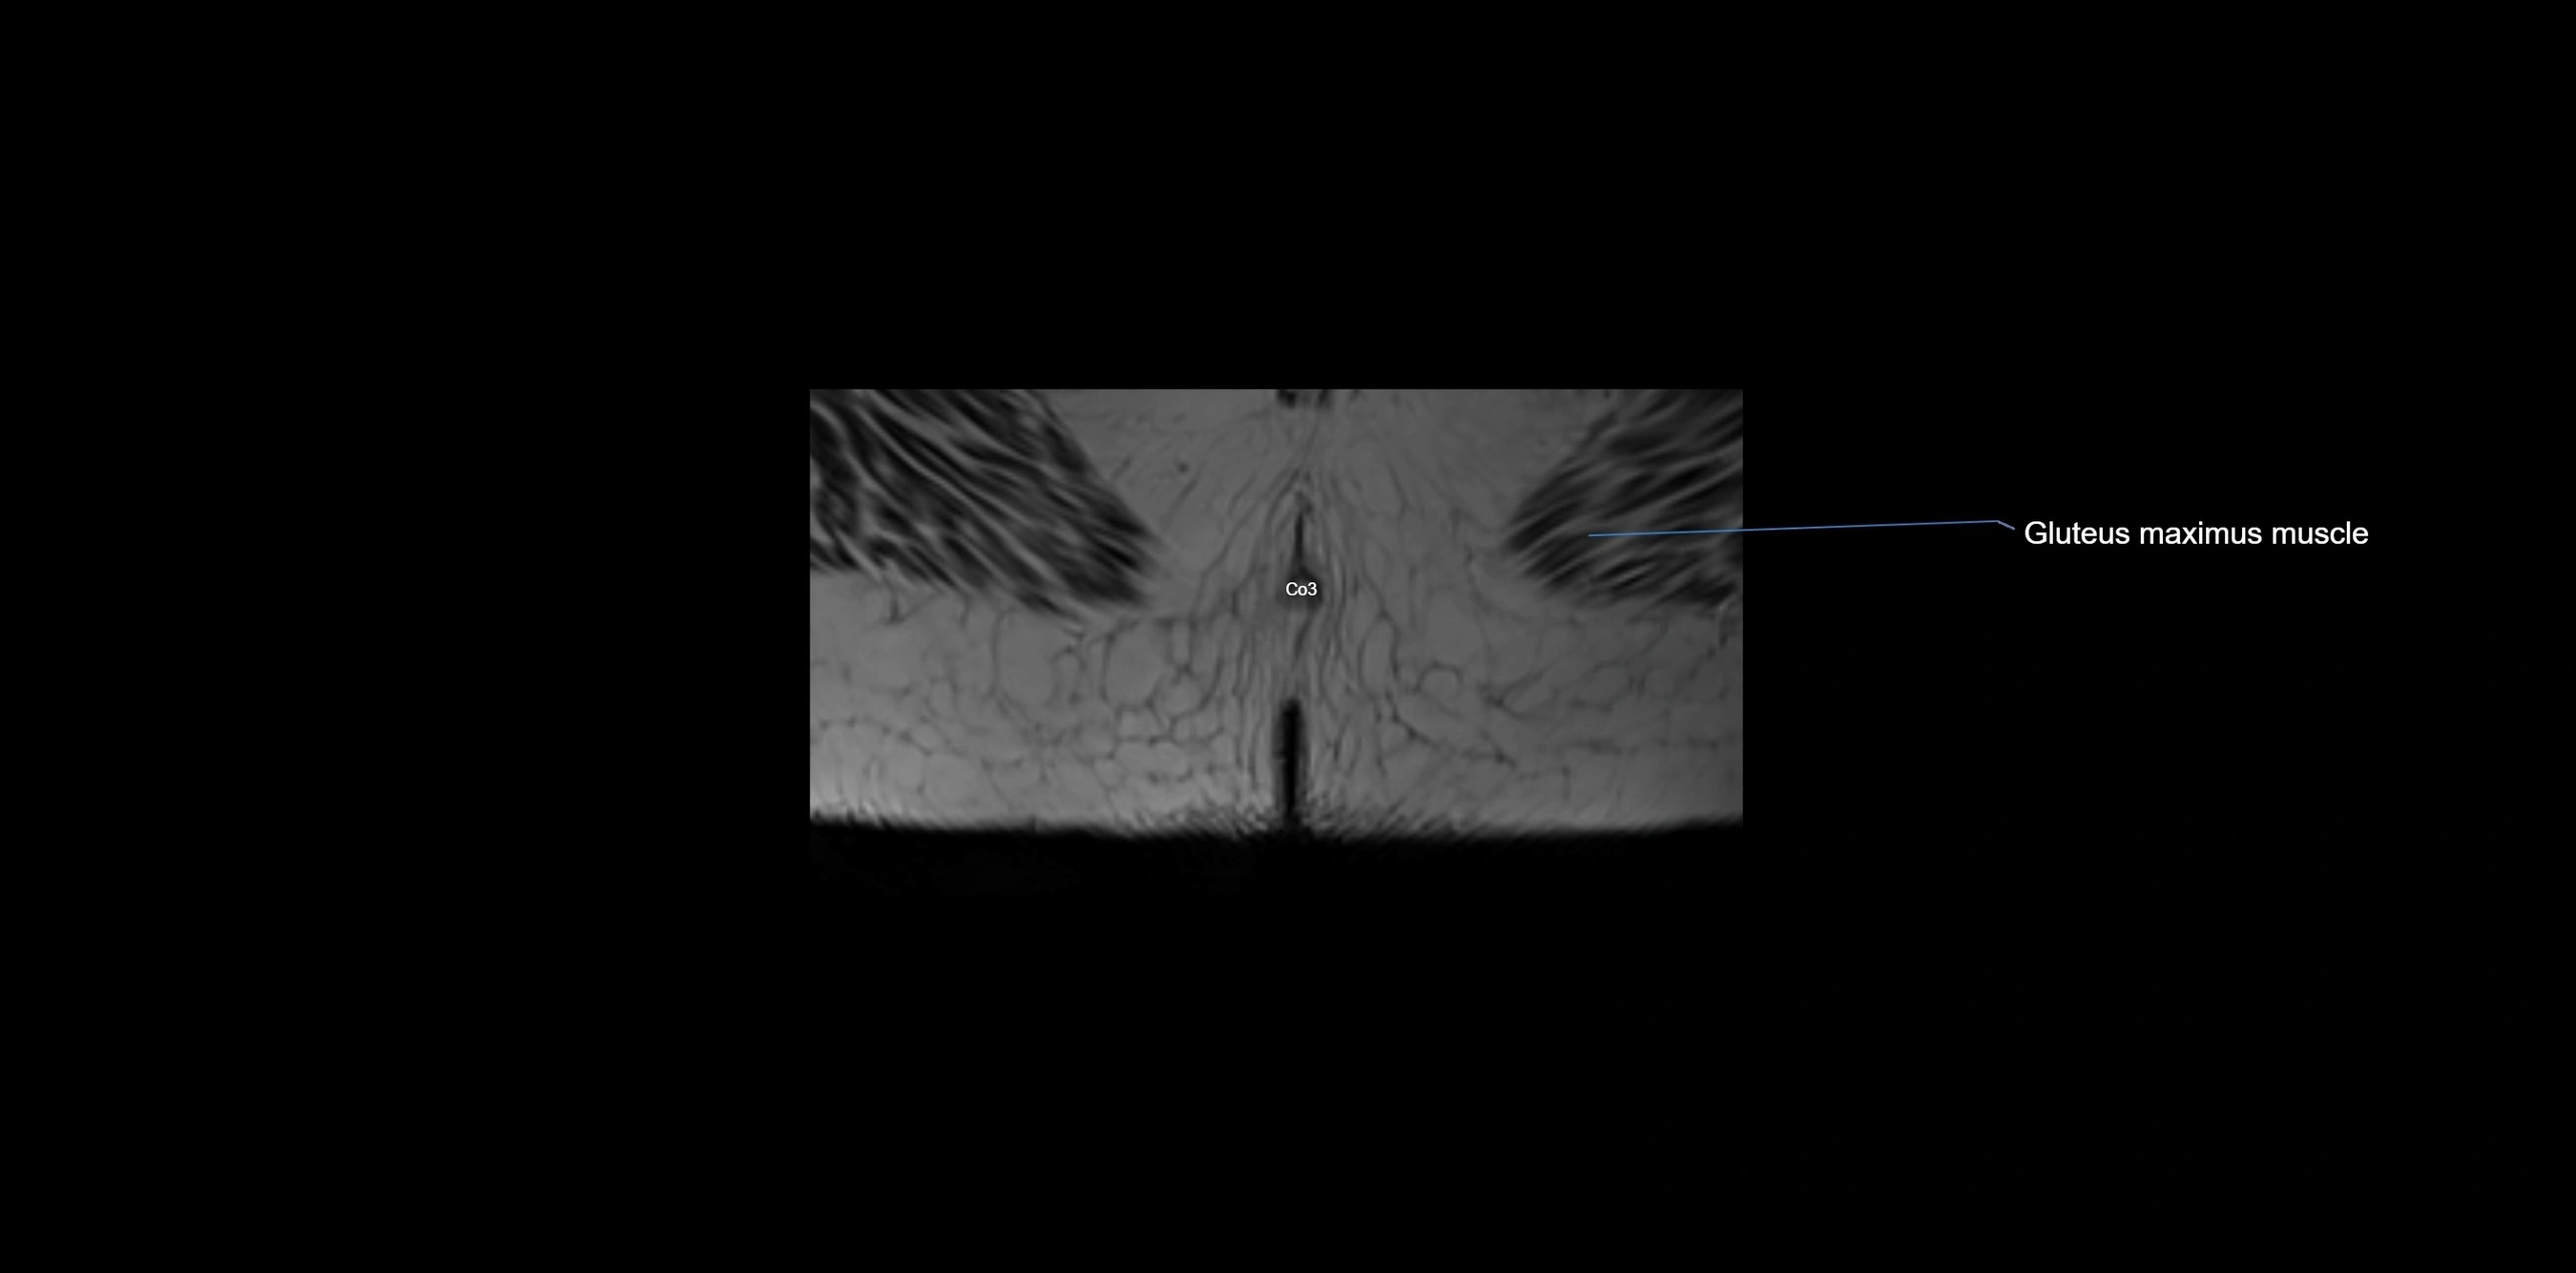

CT image

image